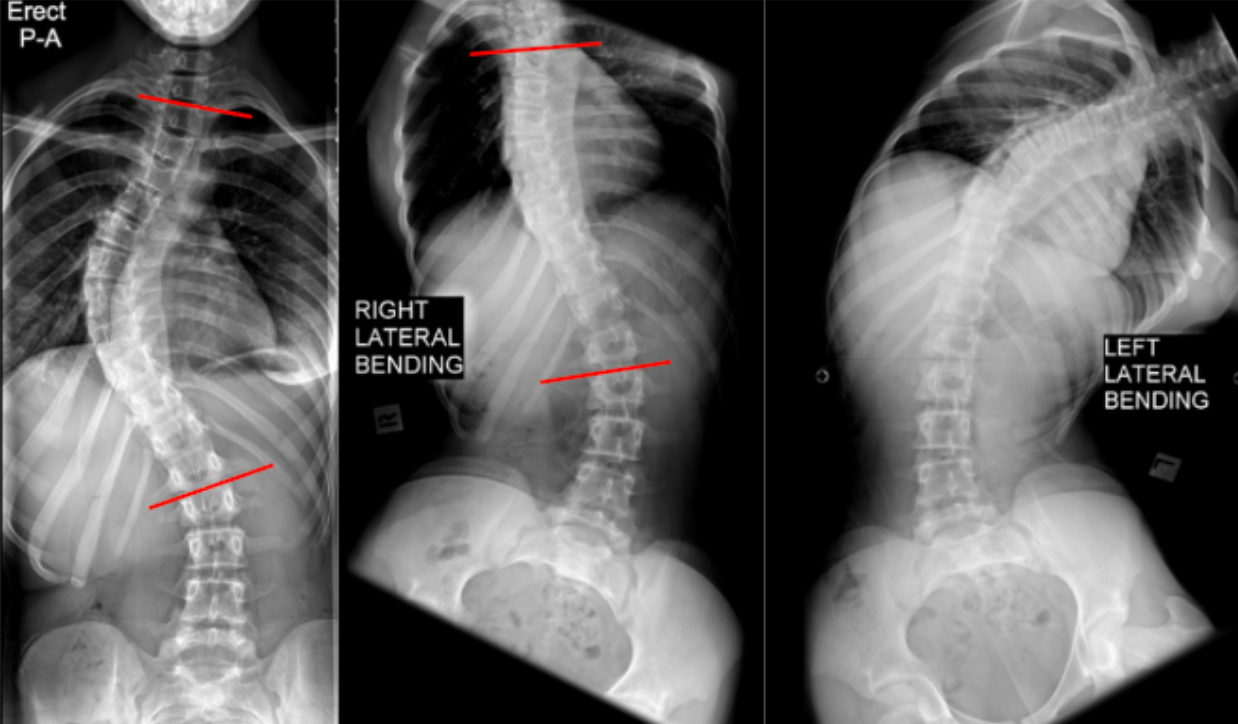

Side-bending Films (Coronal flexibility)

Side-bending films quantify coronal plane flexibility of scoliotic curves by measuring the residual Cobb angle during maximal right and left lateral bending. This measurement is used to determine whether a curve is structural or compensatory, to assess curve stiffness, and to guide operative planning, including the selection of fusion levels.

Coronal flexibility reflects the ability of a spinal curve to correct with active bending and correlates with disc, facet, and ligamentous elasticity.

• On the erect AP film, identify the major curve and measure the baseline Cobb angle using the standard end-vertebra method.

• On the corresponding side-bending film (right or left, depending on curve convexity):

• Identify the same superior and inferior end vertebrae used for the erect Cobb angle.

• Measure the residual Cobb angle while the patient is maximally bent.

Flexibility (%) = Erect Cobb - Bending CobbErect Cobb100

• Record the lowest residual Cobb angle obtained during bending, as this represents maximal achievable correction.